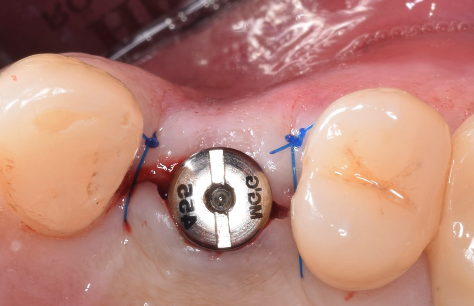

După perioada de osteointegrare a implantului acesta se descoperă, adică se creează o cale de comunicare cu mediul bucal, el până în această etapă fiind acoperit de gingie. Se instalează apoi un bont de vindecare care are rolul să ghideze vindecarea gingiei în jurul implantului.(Fig. 3.5.5 și 3.5.6) Cu acest bont pacientul așteaptă o perioadă variabilă de 14-21 de zile, iar dacă după acest interval gingia este vindecată, se poate trece la etapa următoare – cea de amprentare.